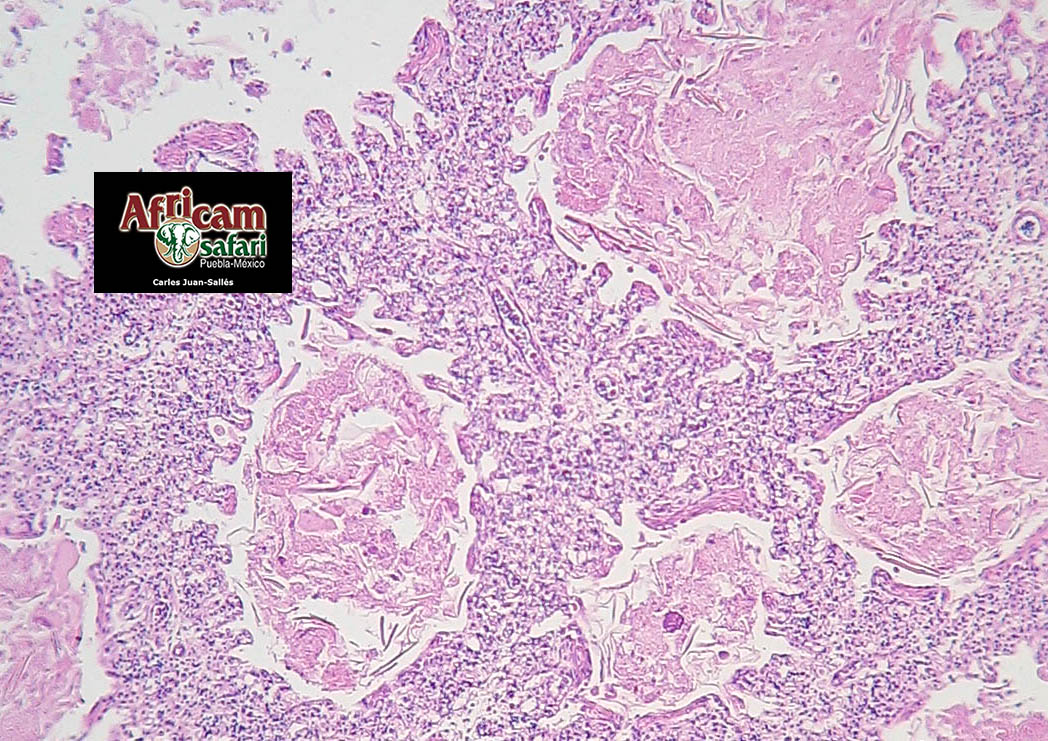

Oreophasis derbianus

Neumonía y aerosaculitis bacterianas embrionarias